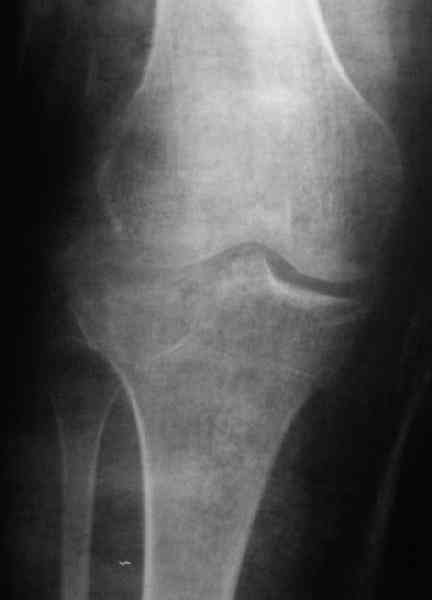

Re: Застарелый перелом 41С3

Уважаемый Абдурашид. Если нет противопоказаний , то из оперативных способов, я бы рекомендовал следующие: Полное замещение наружного мыщелка аллотрансплантатом либо открытая репозиция с элевацией и замещение дефекта ауто или аллокостью. В Ваших условиях , я бы рекомендовал второй способ. Во-время элевации необходимо разъединить фрагменты со стороны сустава ( надсечь скальпелем по линиям перелома, а затем тонким остеотомом их разъединить. При помощи долота произвести неполную остеотомию ( захватите не менее 1,5 - 2 см губчатой кости и поднять фрагменты, визуально отрепонировать и фиксировать 2-3 спицами. Дефект заместить костным ауто или аллатрансплантатом. Окончательная стабилизация пластиной ( лучше с угловой стабильностью, либо АВФ - позволит спокойно устранить угловую деформацию.

Недавно поступила больная через 1,5- 2 месяца.